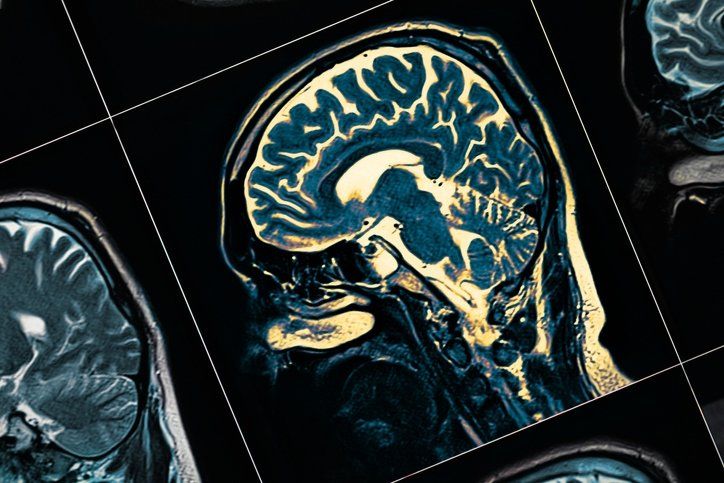

Son araştırmalara göre, yağlı yemekler yemek sadece belinizi büyütmekle kalmaz, aynı zamanda bilişsel işlevinize de zarar veriyor. Güney Avustralya Üniversitesi'nden sinirbilimci Profesör Xin-Fu Zhou ve Doçent Larisa Bobrovskaya tarafından gerçekleştirilen bir çalışmada, hayvanlarda 30 hafta boyunca yüksek yağlı bir diyet verilen ve diyabete neden olan daha sonra anksiyete, depresyon ve kötüleşen Alzheimer hastalığı dahil olmak üzere bilişsel yeteneklerinde düşüş arasında açık bir ilişki gösterilmiştir.

Beyin değişikliklerinin neden olduğu zayıf metabolizma nedeniyle, bilişsel işlevi azalmış fareler de aşırı kilo almaya daha yatkın olduğu ortaya çıktı. Avustralya ve Çin'den araştırmacılar yakın zamanda sonuçlarını Metabolik Beyin Hastalığı dergisinde bildirdiler.

Güney Avustralya Üniversitesi'nde nörolog ve biyokimyacı olan Doçent Larisa Bobrovskaya, çalışmanın diyabet ve obeziteyi 2050 yılına kadar dünya çapında 100 milyon insanı etkilemesi beklenen Alzheimer hastalığı ile ilişkilendiren artan veri kütlesine katkıda bulunduğunu söylüyor.

Bu yapay trans yağlar; katı yağ, margarin, krema, aperatif yiyecekler, hazır kekler ve önceden paketlenmiş kurabiyelerde bulunabilir. Araştırmalar, insanlar daha fazla miktarda trans yağ tükettiğinde, Alzheimer hastalığı, daha zayıf hafıza, daha düşük beyin hacmi ve bilişsel gerileme riskinde artış eğiliminde olduklarını bulmuştur.

243 kişide yapılan bir araştırma, organların çevresinde artan yağın veya viseral yağın beyin dokusu hasarı ile ilişkili olduğunu buldu. 130 kişiyle yapılan başka bir araştırma, metabolik sendromun erken evrelerinde bile beyin dokusunda ölçülebilir bir azalma olduğunu buldu.

Aşırı şekerli içecek alımı, Alzheimer hastalığı riskini arttırdığı gösterilen tip 2 diyabet geliştirme olasılığını artırır.Ek olarak, kandaki yüksek şeker seviyeleri, diyabeti olmayan kişilerde bile bunama riskini artırabilir.

Yüksek fruktoz alımı obezite, yüksek tansiyon, yüksek kan yağları, diyabet ve arteriyel disfonksiyona yol açabilir. Metabolik sendromun bu yönleri, uzun vadede demans geliştirme riskinde bir artışa yol açabilir.